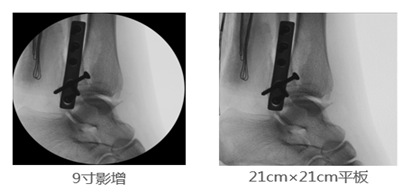

2、成像視野:在圖像尺寸方面, 9英寸平板與9英寸影增相比,平板探測器成像為“方形”,較同尺寸的影像增強器的“圓形”成像而言,有效視野面積擴大了22%,使醫(yī)生的觀察視野更加開闊,極大的提高了手術(shù)的效率,同時提高了各種手術(shù)的安全性。